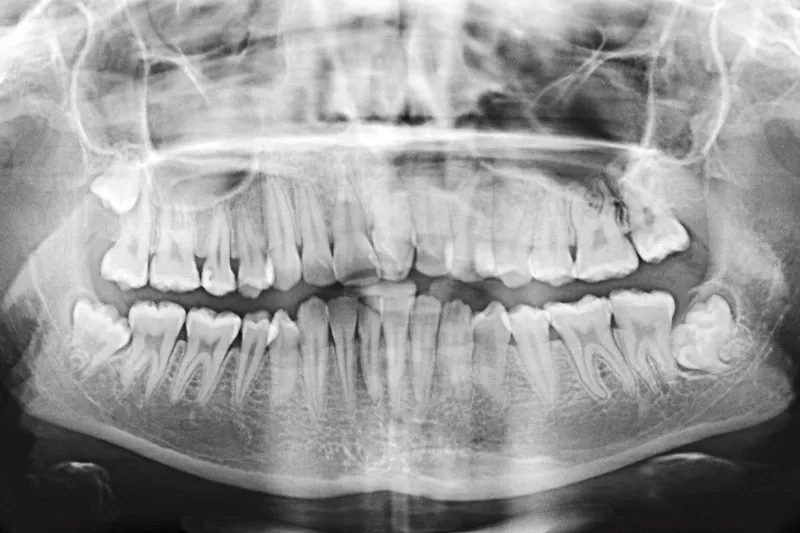

Patienttilfælde – En 12-årig pige udviklede i forbindelse med behandling i generel anæstesi malign hypertermi. Tilstanden blev identificeret hurtigt, og adækvat behandling blev iværksat involverende bl.a. afkøling med håndklæder vædet i sprit og koldt vand samt intravenøs behandling med Dantrolen. Patienten blev stabiliseret og overført i intuberet tilstand til Aarhus Universitetshospital med henblik på videre behandling. Hun blev udskrevet efter 16 dage. Efterfølgende havde hun gener i form af træthed og hovedpine ved langvarig fysisk aktivitet. Disse symptomer er i dag aftaget betydeligt. Hun er således i dag meget lidt generet heraf og har en helt normal hverdag.

Case study – A 12-year-old girl developed malignant hyperthermia during treatment under general anaesthesia. The condition was quickly identified, and adequate treatment was implemented, involving cooling with towels moistened with surgical spirits and cold water as well as intravenous treatment with Dantrolene. The patient was stabilised and transferred intubated to Aarhus University Hospital for further treatment. She was discharged 16 days after admission. Afterwards she had tiredness and headache in conjunction with long-term physical activity. These symptoms have, by time of writing decreased significantly. Therefore, she is today only slightly bothered by them and has a normal life.